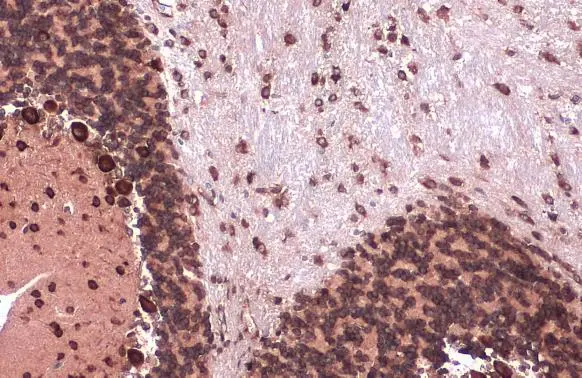

EIF4G3 antibody [N1], N-term detects EIF4G3 protein at cytosol on rat hind brain by immunohistochemical analysis. Sample: Paraffin-embedded rat hind brain. EIF4G3 antibody [N1], N-term (GTX118109) dilution: 1:500.

Antigen Retrieval: Trilogy? (EDTA based, pH 8.0) buffer, 15min